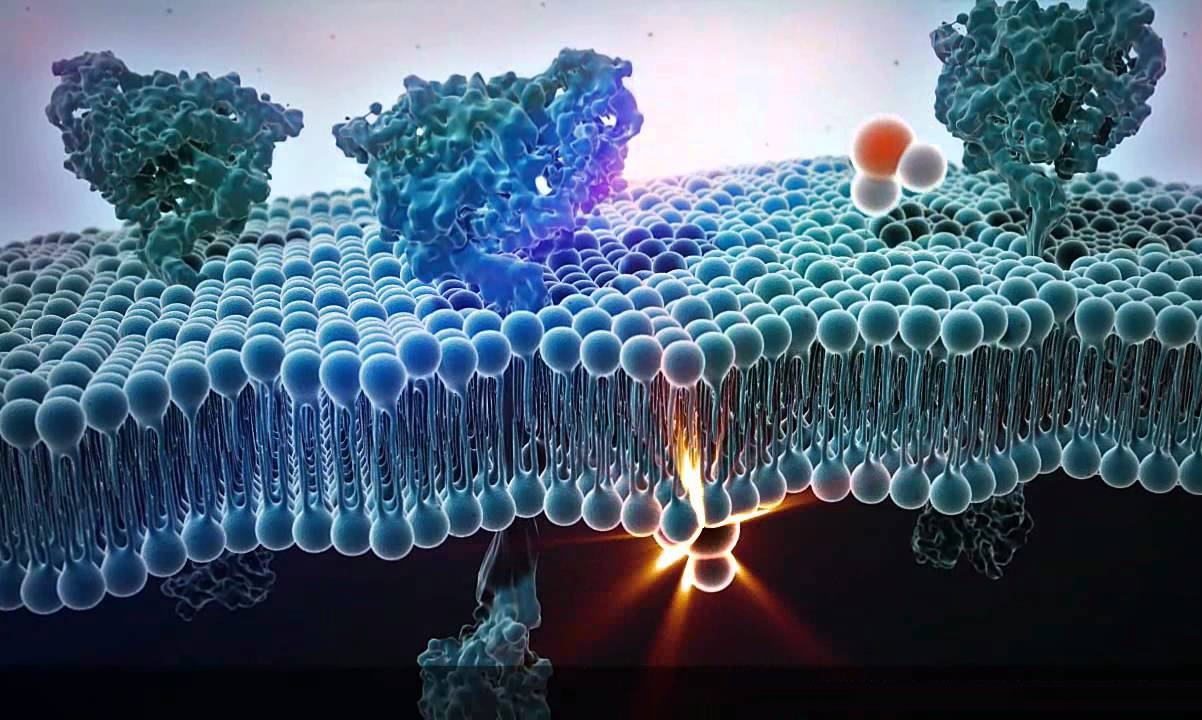

قیمت: 78٬000 تومان - دسته بندی فایل: پاورپوینت

قیمت: 78٬000 تومان - دسته بندی فایل: پاورپوینتپاورپوینت اهمیت لیپیدها

فروش ویژه پاور پوینت حرفه ای اهمیت لیپیدها با تخفیف استثنایی فقط 92 هزار تومان تعداد اسلاید: 44 اسلاید